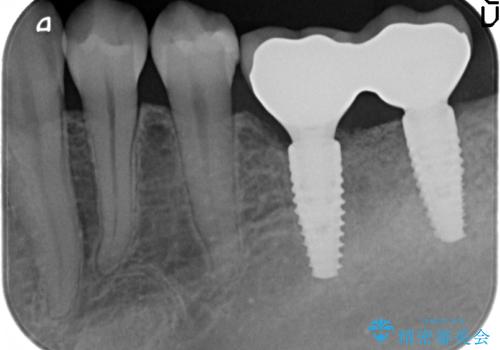

- 80万円(インプラント×2・骨造成・アバットメント×2)・ジルコニアクラウン×2)費用は治療当時の料金となります

インプラントの長期的な予後を見込むには、インプラント周囲の安定した十分な骨量や清掃性、角化歯肉の存在が重要です。